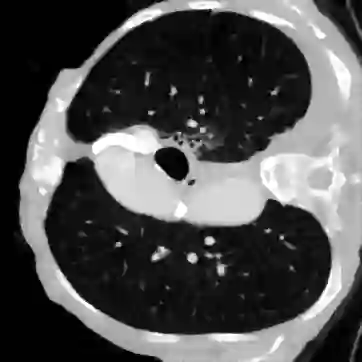

Deep learning-based image reconstruction approaches have demonstrated impressive empirical performance in many imaging modalities. These approaches generally require a large amount of high-quality training data, which is often not available. To circumvent this issue, we develop a novel unsupervised knowledge-transfer paradigm for learned iterative reconstruction within a Bayesian framework. The proposed approach learns an iterative reconstruction network in two phases. The first phase trains a reconstruction network with a set of ordered pairs comprising of ground truth images and measurement data. The second phase fine-tunes the pretrained network to the measurement data without supervision. Furthermore, the framework delivers uncertainty information over the reconstructed image. We present extensive experimental results on low-dose and sparse-view computed tomography, showing that the proposed framework significantly improves reconstruction quality not only visually, but also quantitatively in terms of PSNR and SSIM, and is competitive with several state-of-the-art supervised and unsupervised reconstruction techniques.

翻译:深层学习图像重建方法在许多成像模式中表现出了令人印象深刻的经验性表现,这些方法一般需要大量往往无法获得的高质量培训数据。为回避这一问题,我们为在巴伊西亚框架内进行学习的迭代重建开发开发了一种新的不受监督的知识转移模式。拟议方法分两个阶段学习了迭接重建网络。第一阶段培训重建网络,配有一套由地面真实图像和测量数据组成的定单配对。第二阶段对预先训练的网络进行微调,使其与未经监督的测量数据挂钩。此外,该框架还就重建后的图像提供了不确定信息。我们介绍了关于低剂量和少见的计算图象学的广泛实验结果,表明拟议的框架不仅在视觉上,而且在数量上大大改进了重建质量,而且在PSNR和SSIM方面,并且与一些最先进的、受监督和不受监督的、不受监督的重建技术具有竞争力。